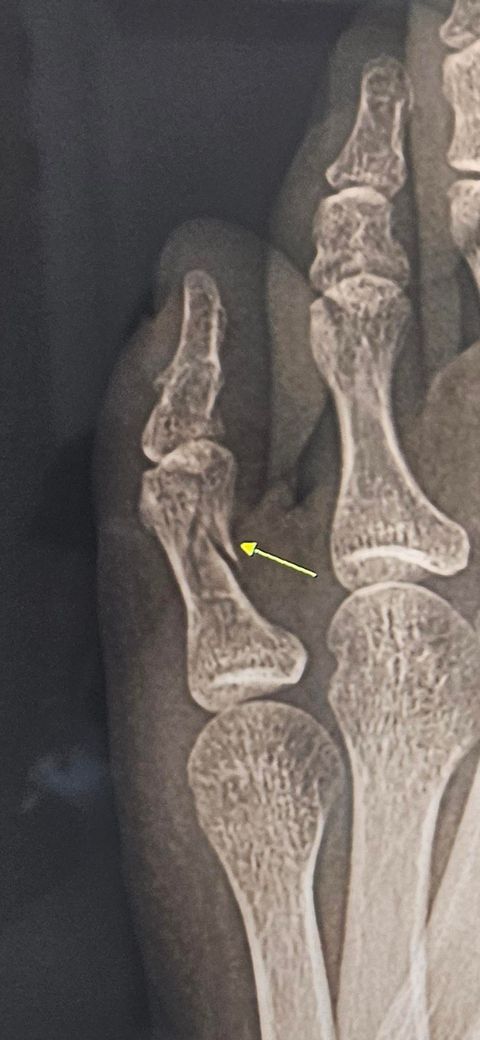

새끼발가락 골절 비수술 상태봐주셔요..

새끼발가락 골절되어 비수술 및 입원중이며, 반깁스 10일, 통깁스 1일차입니다. 통깁스 말고 발가락이랑 발등에 걸쳐서 하는 그물망깁스하고 일상생활해도될까요?.. 제 골절이 많이 심한편인지요.. 통깁스가 너무무거워서 바꾸고싶네요..ㅜ

현재 엑스레이 사진인지, 다쳤을때 사진인지 알아야 할 것 같은데 처음찍은 엑스레이 골절의 상태가 눈으로 보일 정도면 아직은 통기브스가 안전하긴 합니다. 다만 전문의 판단하에 그물 기브스도 가능 할 것 같은데.. 상의 해보시는게 가장 정확합니다.

• 안녕하세요. 김경태 정형외과 전문의입니다.

꽤 많이 깨져보입니다.

전위는 그리 심해보이진 않아서 보존적치료로 결과가 좋을것 같습니다.

불편하셔도 캐스트를 하는게 맞습니다.